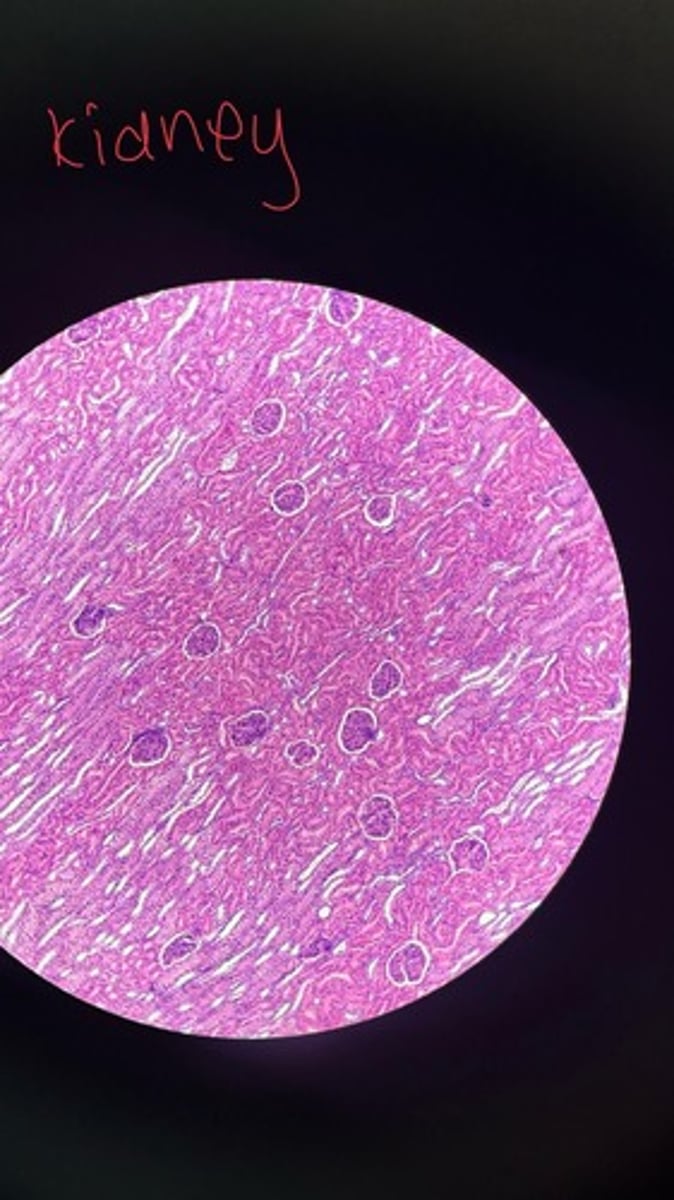

Kidney HE

Kidney HE

Kidney HE

Kidney HE

Kidney HE